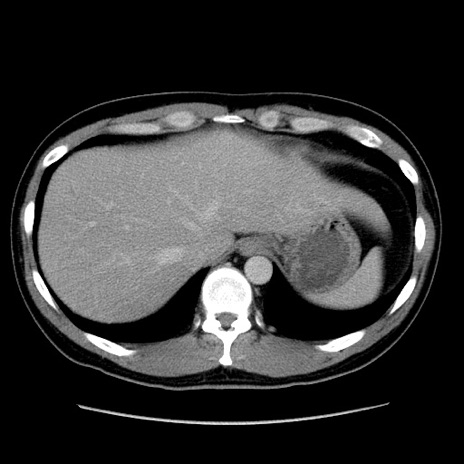

症例4(横断像)

【症例】30歳代男性

【主訴】腹痛、嘔吐

【現病歴】昨晩から突然の腹痛あり、その後嘔吐、軟便も出現。腹痛が改善しないため救急搬送となる。2日前にしめ鯖の食事歴あり。

【身体所見】意識清明、苦悶様、BP 135/90mmHg、BT 35.7℃、腹部:平坦、やや硬、心窩部〜臍部に自発痛、圧痛あり、筋性防御+、反跳痛-

【データ】WBC 8100、CRP 0.57